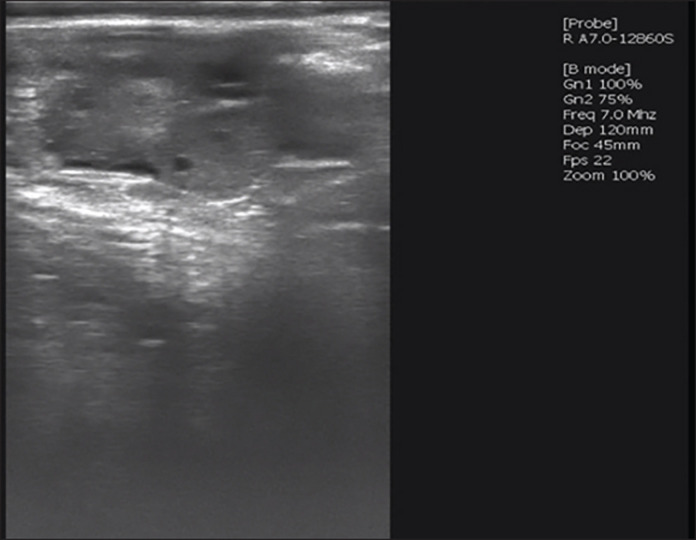

Aim: This study aimed to compared two superovulation protocols-conventional intramuscular injection (P1) and combined epidural-intramuscular injection (P2)-in Wagyu donor cows to evaluate their effects on corpus luteum (CL) formation, embryo yield, and quality.

Methods: The study was conducted from May to November 2024. Twelve cows were divided into two treatment groups (n = 6 per group), with follicle-stimulating hormone administered either through multiple intramuscular injections (P1) or a single-dose epidural-intramuscular injection (P2). Selection criteria included superior genetics, normal reproduction, regular estrus cycles (18-24 days), high fertility, prior calving, and disease-free status. Donor cows had a Body Condition Score of 2.5-3.5 and were confirmed to have normal reproductive organs via rectal examination. They were housed in a free-stall system and fed a controlled diet. Evaluated reproductive parameters included CL formation, embryo recovery rates (ERRs), and embryo quality.Results: There were no statistically significant differences between P1 and P2 in CL formation (p = 0.480), ERRs (p = 0.810), or embryo quality (p = 0.871). Both protocols supported comparable follicular development, embryo recovery, and transferable embryos across developmental stages (morula, early blastocyst, and blastocyst). While P2 produced slightly more CL and blastocysts, the differences were not significant. Both protocols yielded similar proportions of unsuitable embryos, indicating no adverse effects on fertilization or embryonic viability.